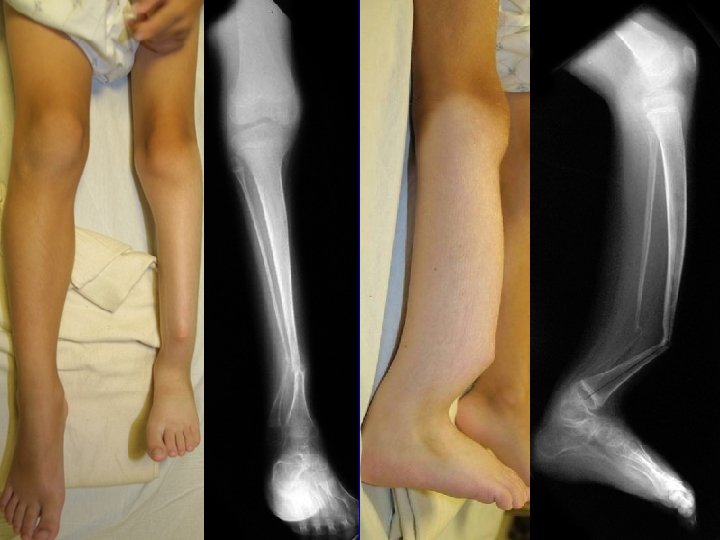

preop postop